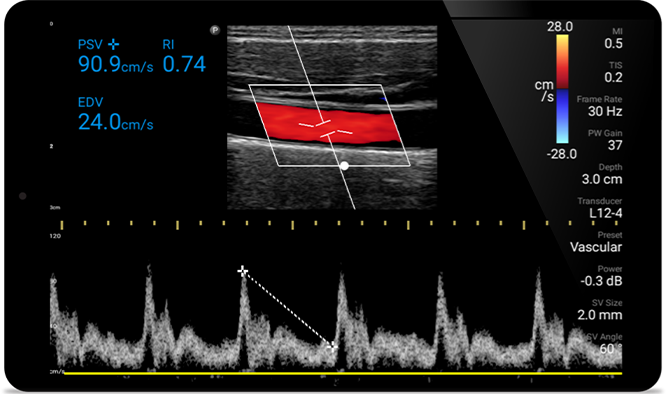

Mit hoher Detailgenauigkeit und hervorragender Gewebedefinition aus verschiedenen Winkeln unterstützt Sie Lumify bei zuverlässigen Echtzeitentscheidungen in allen Versorgungsphasen.

POC ultrasound for soft tissue (Weichgewebe-Ultraschall am Point of Care)